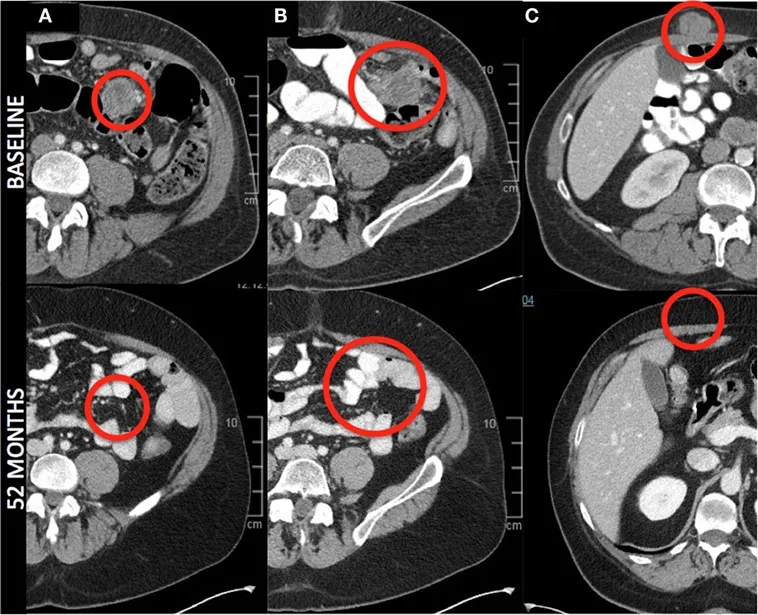

值得关注的是,1例患者在52个月时达到完全缓解(详见下图),并持续至53个月(≈4.4年),且参加试验后未接受后续治疗。下图的放射影像学轴向图像显示,该患者肠系膜(详见下图A、B)和腹壁(详见下图C)病变完全消退,肝脏、腹后壁等其他病变亦完全消退。

▲图源“frontiers”,版权归原作者所有,如无意中侵犯了知识产权,请联系我们删除